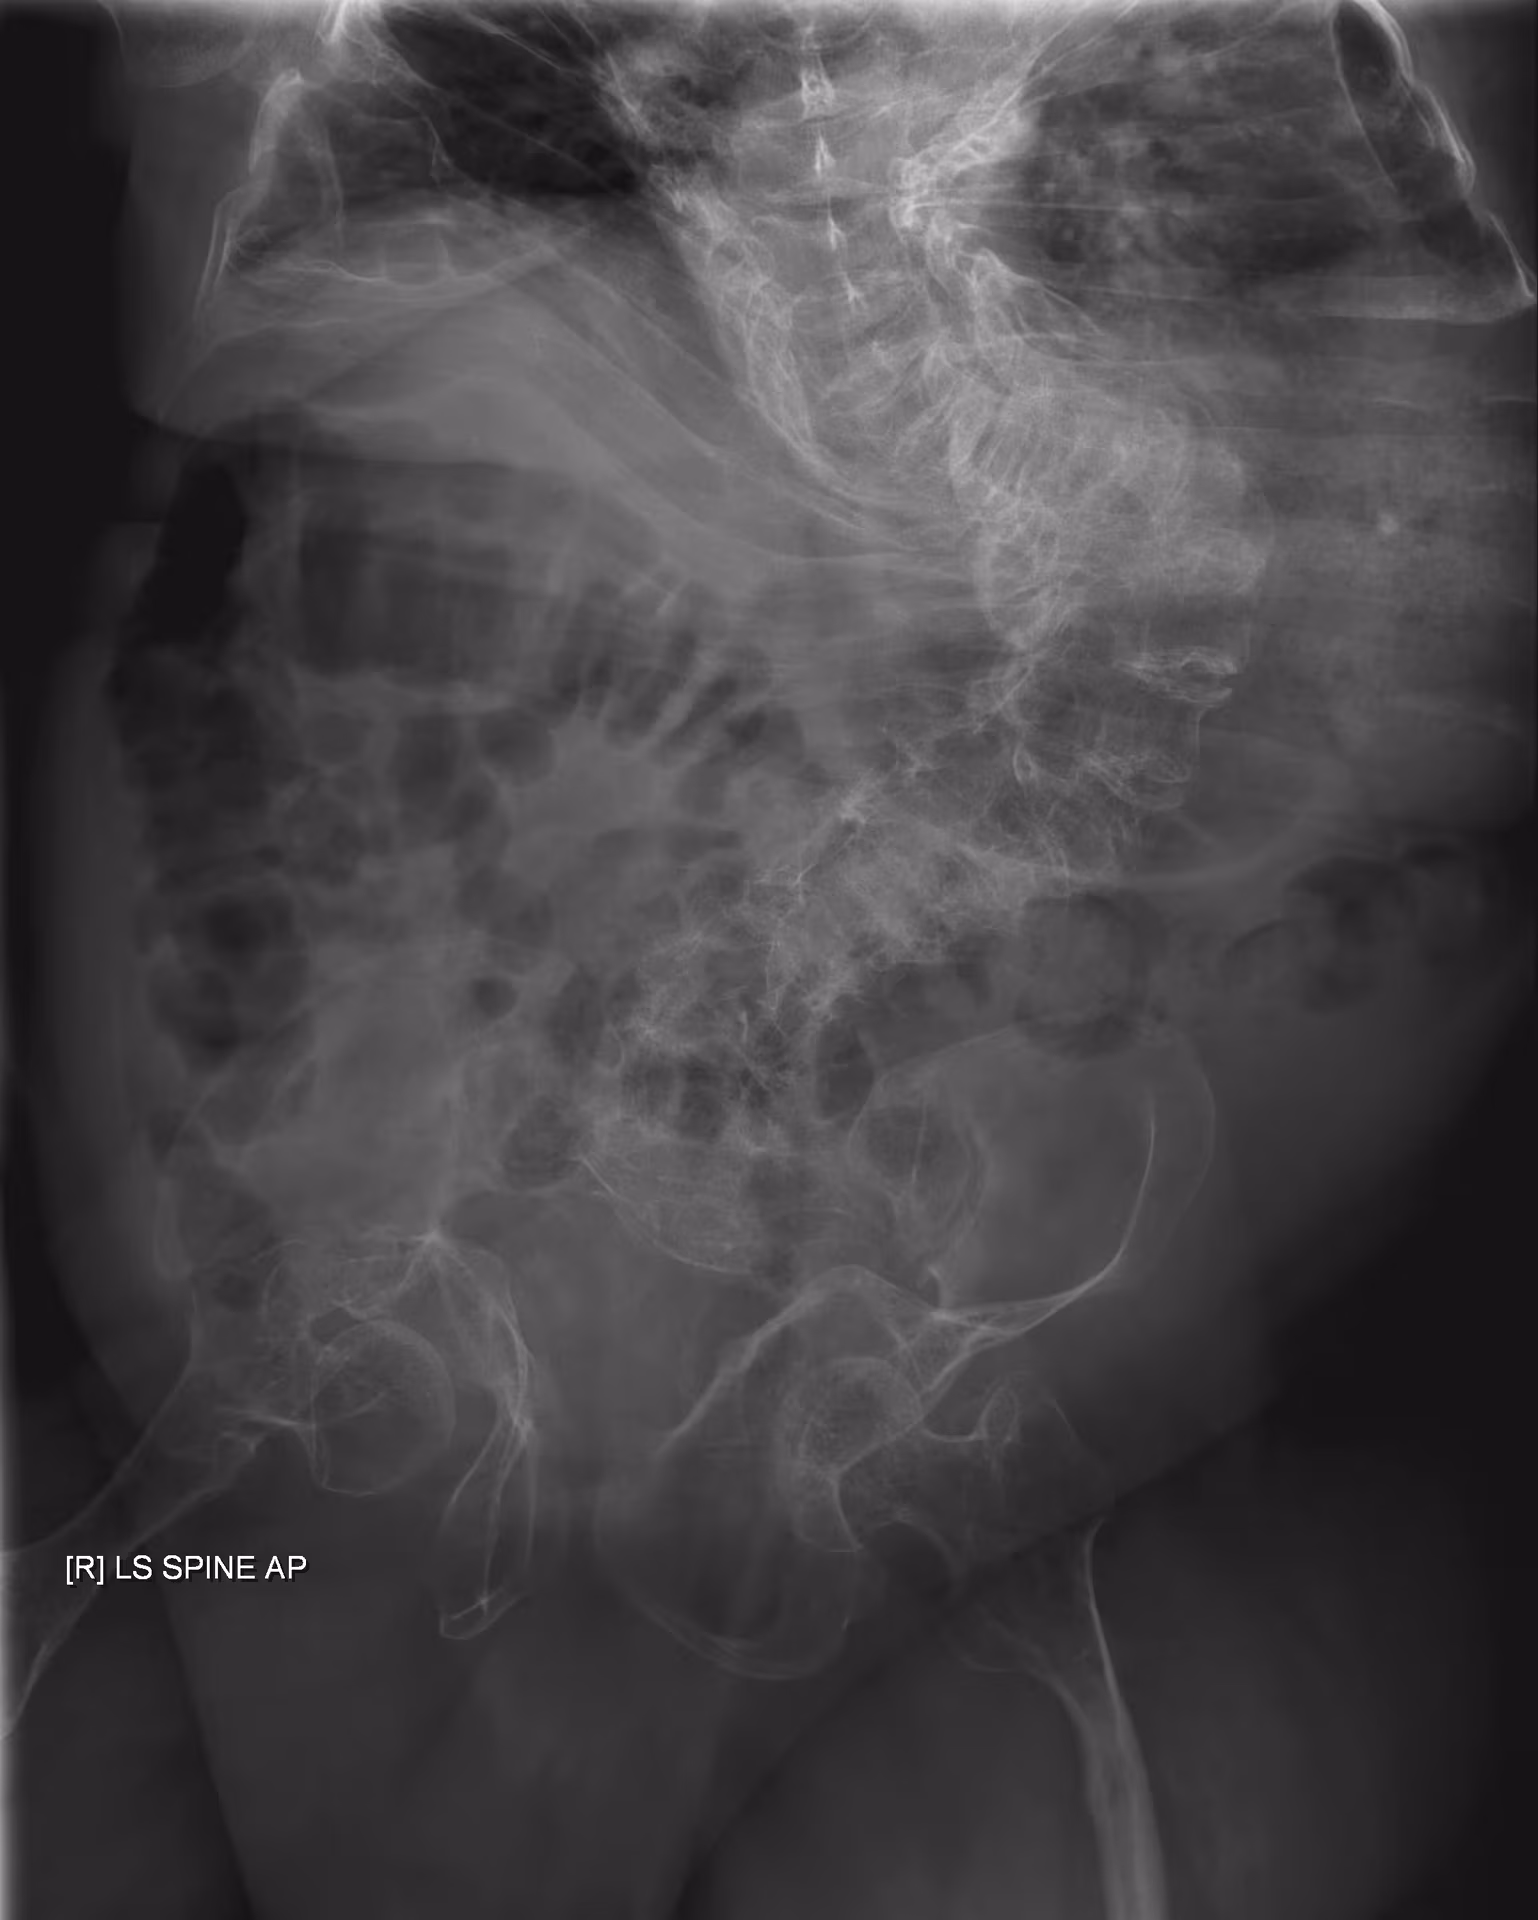

X-ray of a 24-year-old American man, who had suffered more than one hundred bone fractures in his lifetime, and received a childhood clinical diagnosis of type IVB OI. Genetic diagnosis in 2018 identified a previously uncatalogued pathogenic variant in the gene which encodes proα2(I) chains of type I procollagen, COL1A2, at exon 19, substitution c.974G>A. Due to childhood neglect and poverty, subject never received surgery to implant intramedullary rods. Malunions are evident as the humerus and femur were broken in adolescence but orthopedic care did not follow. Severe scoliosis, as well as kyphosis, are also evident. The unavoidably low contrast in the film is due to a combination of subject's obesity and low bone mineral density (BMD). Subject's BMD Z-score was -4.1 according to results of a dual-energy X-ray absorptiometry (DXA) scan also done in 2018. This X-ray is of the left forearm and also shows most of the left upper arm and part of the left hand.

X-ray of a 24-year-old man clinically diagnosed with Type IVB OI. Genetic diagnosis in 2018 resulted in no identifiable type, but identified a previously uncataloged pathogenic variant in the gene which encodes proα2(I) chains of type I procollagen, COL1A2, at exon 19, c.974G>A. Due to childhood neglect, subject never received rodding surgeries, and there is also evidence the femur was broken and not set properly in a hospital, causing a malunion. Severe scoliosis is also evident. The unavoidably low contrast in the film is due to a combination of subject's obesity and poor bone density.